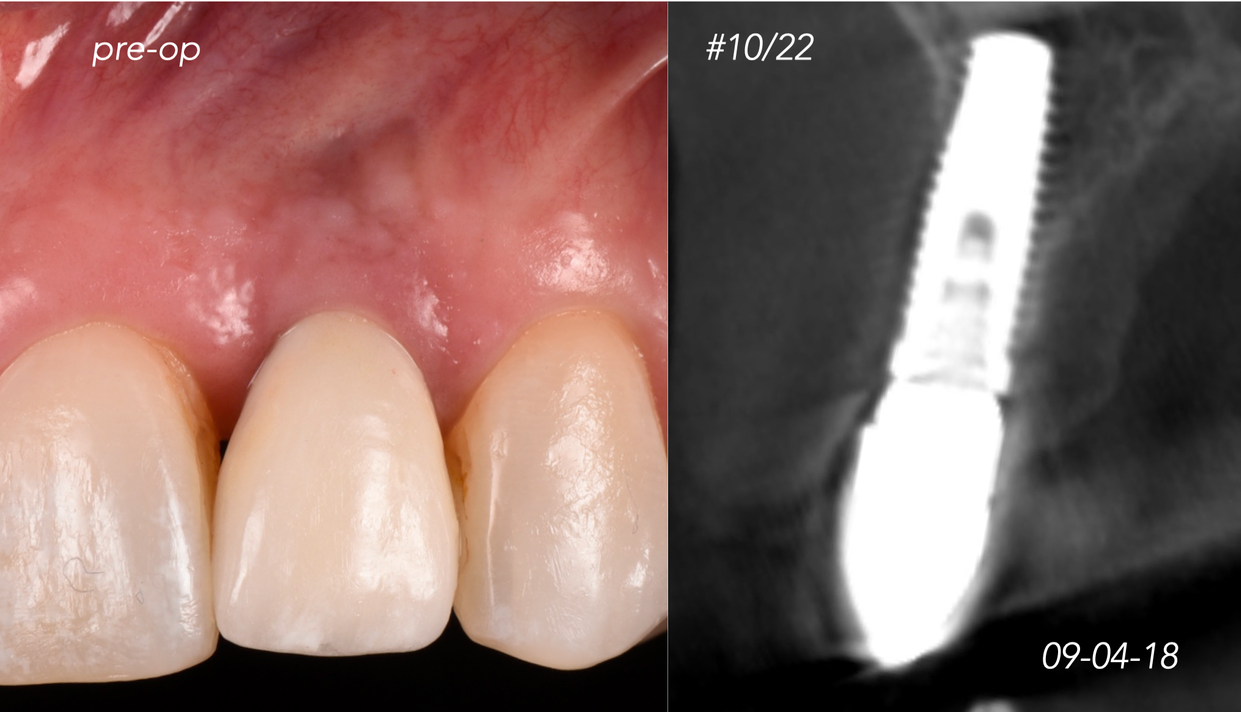

Clinical Cases CASE 1. COMPLEX IATROGENIC DEFECT CASE 2. CONGENITALLY MISSING LATERAL INCISORS CASE 3. VERTICAL AUGMENTATION CASE 4. VERTICAL AUGMENTATION CASE 5. IMPLANT BONE DEHISCENCE CASE 6. IMPLANT BONE DEHISCENCE CASE 7. KNIFE-EDGE RIDGE CASE 8. IMMEDIATE IMPLANT AND SIMULTANEOUS S.M.A.R.T.® HORIZONTAL AUGMENTATION CASE 9. IMMEDIATE IMPLANT AND SIMULTANEOUS S.M.A.R.T.® HORIZONTAL AUGMENTATION